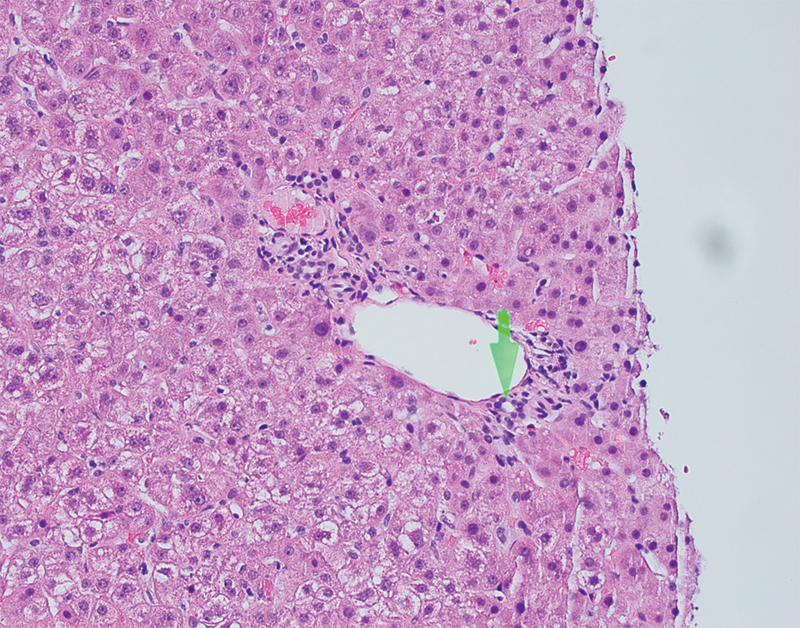

由严重急性呼吸系统综合征冠状病毒2引起的2019冠状病毒病(COVID-19)已引发全球健康危机。该病毒可引起不同程度的肝损伤,但其机制尚未阐明,特别是在妊娠期。我们报告了一名患有COVID-19的30岁病态肥胖女性,妊娠28周合并明显的转氨炎,肝酶水平峰值为501/ 1313(天冬氨酸转氨酶/丙氨酸转氨酶)。肝活检显示反应性改变,符合药物作用和轻度脂肪变性。在怀孕和非怀孕的COVID-19患者中都发现了明显的转氨炎。我们的病例显示了COVID-19患者肝损伤的多因素性质,包括轻度潜在肝脂肪变性,并可能伴有病毒增强药物作用。

Coronavirus disease 2019 (COVID-19), caused by severe acute respiratory syndrome coronavirus 2, has led to a global health crisis. The virus can cause varying severity of liver injury, but the mechanism has not yet been elucidated, especially in pregnancy. We present a morbidly obese 30-year-old woman with COVID-19 at 28 weeks' gestation complicated by significant transaminitis with peak liver enzymes levels of 501/1,313 (aspartate aminotransferase/alanine aminotransferase). Liver biopsy showed reactive changes consistent with medication effect and mild steatosis. Significant transaminitis has been found in both pregnant and nonpregnant patients with COVID-19. Our case demonstrates the multifactorial nature of liver injury in COVID-19 patients including mild underlying liver steatosis combined with possible viral potentiation of medication effect.